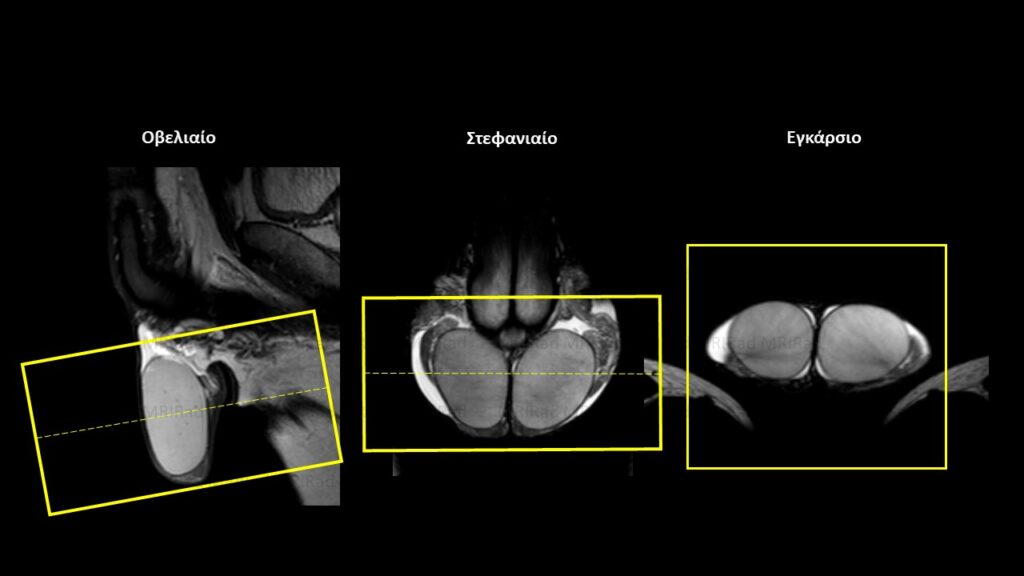

Σχεδιασμός τομών

Οβελιαίο Επίπεδο (Sagittal): Σχεδιάζουμε το οβελιαίο επίπεδο χρησιμοποιώντας εικόνες σε εγκάρσιο και στεφανιαίο προσανατολισμό. Το πακέτο τοποθετείται κατά τέτοιο τρόπο ώστε οι τομές να είναι παράλληλες (κατά το δυνατόν) τόσο με τον προσθοπίσθιο άξονα των όρχεων στο εγκάρσιο επίπεδο όσο και με τον κεφαλουραίο άξονα των όρχεων στο στεφανιαίο επίπεδο. Προσοχή στο πακέτο μας οι τομές να περιλαμβάνουν αμφότερες τις επιδιδυμίδες και όλο το όσχεο.

Εγκάρσιο Επίπεδο (Axial/Transversal): Σχεδιάζουμε το εγκάρσιο επίπεδο χρησιμοποιώντας εικόνες σε οβελιαίο και στεφανιαίο προσανατολισμό. Το πακέτο τοποθετείται κατά τέτοιο τρόπο ώστε οι τομές να είναι κάθετες (κατά το δυνατόν) με τον κεφαλουραίο άξονα των όρχεων και στα δύο επίπεδα. Προσοχή στο πακέτο μας οι τομές να περιλαμβάνουν αμφότερες τις επιδιδυμίδες και όλο το όσχεο.

Στεφανιαίο Επίπεδο (Coronal): Σχεδιάζουμε το στεφανιαίο επίπεδο χρησιμοποιώντας εικόνες σε εγκάρσιο και οβελιαίο προσανατολισμό. Το πακέτο τοποθετείται κατά τέτοιο τρόπο ώστε οι τομές να είναι κάθετες (κατά το δυνατόν) με τον προσθιοπίσθιο άξονα των όρχεων στο εγκάρσιο επίπεδο και παράλληλες με τον κεφαλουραίο άξονα των όρχεων στο οβελιαίο επίπεδο. Προσοχή στο πακέτο μας οι τομές να περιλαμβάνουν αμφότερες τις επιδιδυμίδες και όλο το όσχεο.